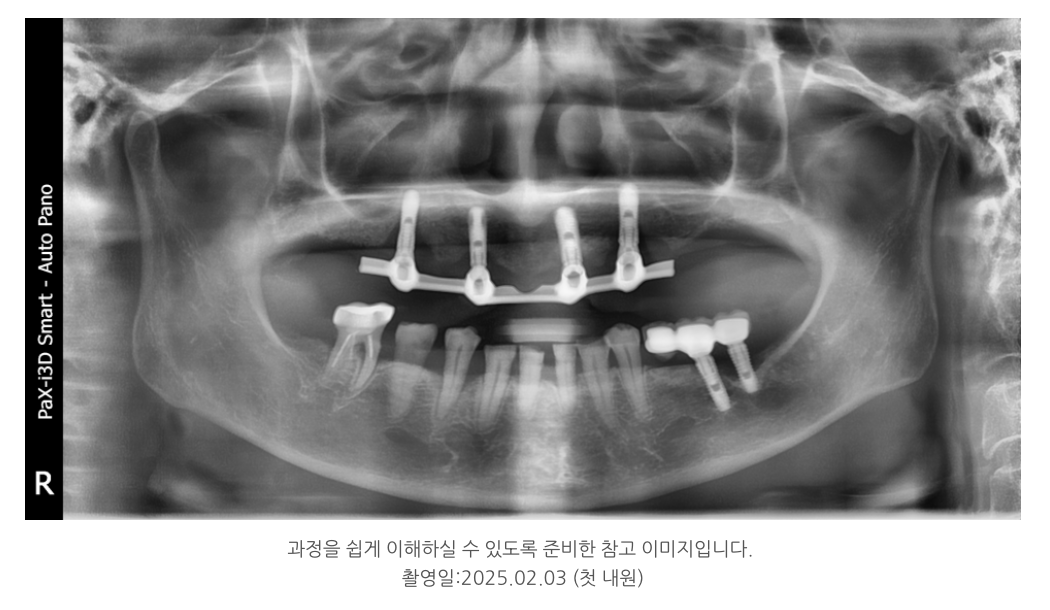

이 환자분 역시 위턱에 임플란트 4개를 심고

bar(바) 형태로 틀니를 걸어 사용하는 구조였는데,

특정 부위에 힘이 과도하게 전달되어 뼈 흡수가 일어났습니다.

???? 전체 임플란트로의 전환

이 경우는 단순히 틀니를 새로 만드는 것으로는

해결이 어렵기 때문에

최종적으로 위턱 전체 임플란트를 계획했습니다.